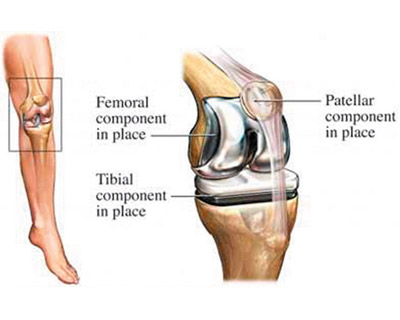

The surgeon then uses special equipment to precisely cut bone and cartilage from the damaged portion of the femur (thighbone) and resurfaces it. This is followed by placing a metallic implant with the help of bone cement that seals it and recreates the surface of the joint.

Now the shinbone (tibia) is resurfaced in a similar way and a medical-grade plastic tibial component is placed to provide a smooth gliding surface. The bottom portion of the plastic implant is called tibial tray and is set with the bone using bone cement.

Lastly the patella is set at its original place. But before the surgeon fits it in, he uses another plastic component to make sure it sets properly with the rest of the implant.